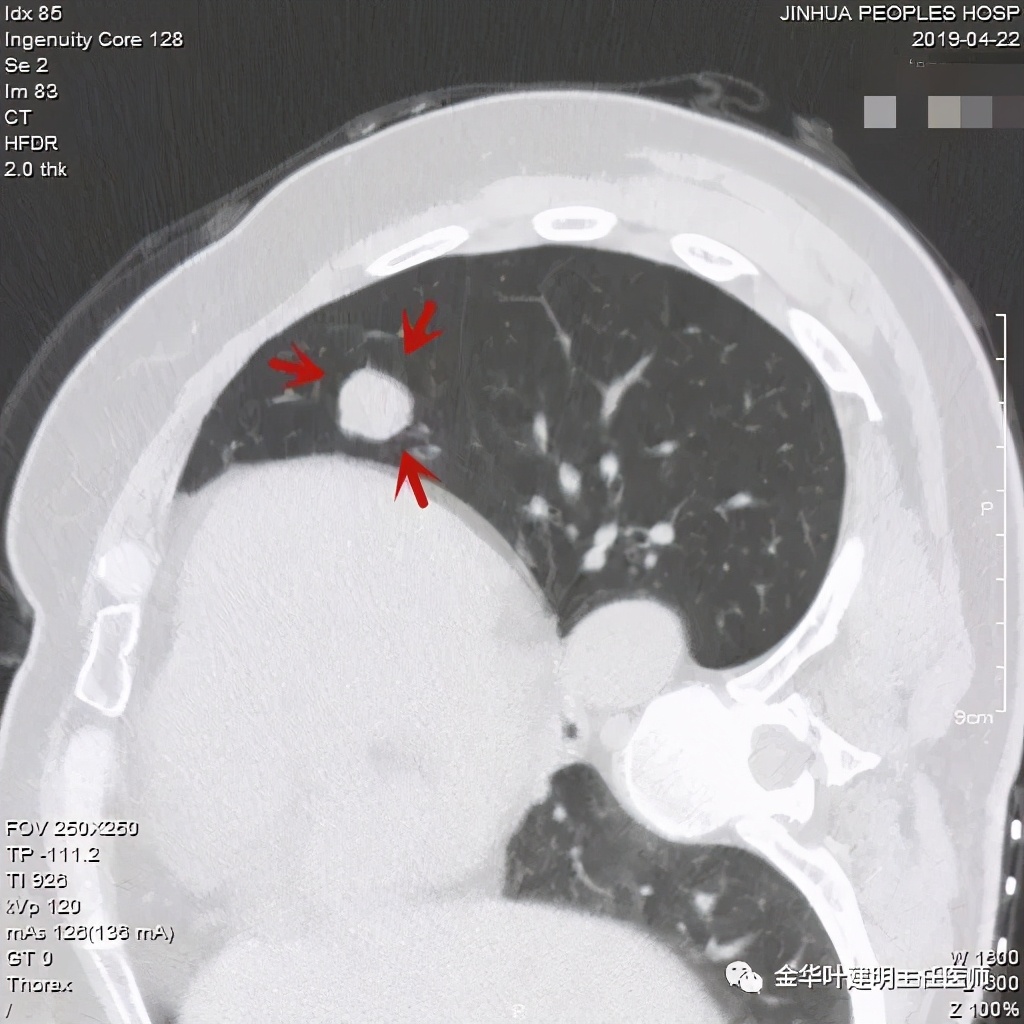

事前来看,达2.4厘米的不均质实性肿块,增强有轻度不均匀强化,血管贴边走行,支气管疑有截断,恶性不能除外,而且可能性较大。但现在经过手术已已经证实是错构瘤的情况下,我们回头来看,其实有许多不符合恶性的地方:

1、病灶的每个层面,边缘都过于光滑了。肺癌一般到这个大小总要有棘突、分叶、毛刺、牵拉周围胸膜等边缘异常的征象;

2、肿瘤大于2厘米以上,又紧贴血管,多有血管走行异常、受侵或血管进入等征象;

3、支气管截断不确切,若术前能三维重建或支气管镜检查可能能明确是否有支气管受累;而且占位致支气管截断,容易有刺激性咳嗽症状;

4、轻度强化是否可靠?肿瘤达2.4厘米,是否强化会比较明显,因为血供要求较多呀。

其实我们发现,包括今天这例,只要是错构瘤,“边缘非常光滑”是每一像都具备的!虽然有的似有支气管截断、有的似有血管征、有的似有分叶,但总的只要是边缘非常光滑的实性占位,就要想到错构瘤的可能,若有点状钙化密度,更是强烈要考虑。错构瘤如何靠近胸膜,其实可以切开一点肺实质,挤一下,肿瘤就会滚出来。